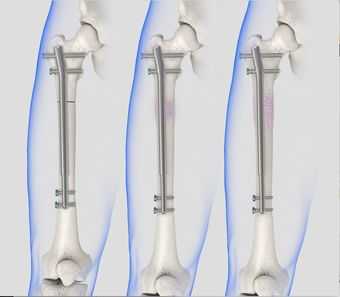

Интрамедуллярный метод

При интрамедуллярной технике дистальный и проксимальный отломки соединяются специальными стержнями или штифтами, проведенными через костномозговой канал каждого из них. Сегодня преимущество на стороне эндосистем блокирующего типа. На их противоположных концах имеются уже готовые отверстия для винтов или своеобразные загибы, повышающие степень стабилизации системы. Интрамедуллярными устройствами, которые бывают ригидными или полуэластичными, возможно зафиксировать даже множественные осколки.

Введение стержня/штифта в диафиз может быть совершено как после предварительной подготовки канала путем его рассверливания, так и без перфорации. Все внутрикостные конструкции подлежат удалению, что означает проведение еще одного вмешательства после полного костного сращения. Повторная процедура по извлечению фиксаторов в большинстве случаев не сопряжена интра- и послеоперационными трудностями.

Остеосинтез бедренной кости также делят на отдельные виды в зависимости от техники вмешательства:

интрамедуллярный остеосинтез — установка крепежной спицы или штифта внутрь спинномозгового канала;

Интрамедуллярный остеосинтез — метод первого выбора в хирургическом лечении переломов. Он проводится в несколько этапов: